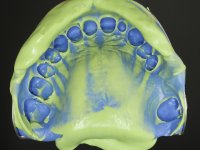

O tratamento iniciou-se com a re -preparação do coto do espigão falso coto fundido, com o objetivo de colocar as linhas de acabamento cervical com uma localização intra-sulcular e simultaneamente confecionar uma coroa provisória adaptada. Com um tratamento ortodôntico muito simples, fechou-se o diastema entre os incisivos centrais superiores e estabilizou-se esta posição com um arame colocado na superfície palatina dos centrais, funcionando como contenção. Posteriormente procurou-se fazer uma tração ortodôntica lenta do dente 2.2 com o intuito de diminuir, ainda que muito ligeiramente a perda óssea vertical nessa zona. Finalizada a tração, foi feita a extração do dente 2.2 e a zona foi reabilitada provisoriamente com uma coroa de resina composta colada aos dentes adjacentes. Foi colocado um implante dentário na zona do dente 2.2 sendo novamente colada a coroa provisória em resina, reabilitando provisoriamente a paciente durante o período de osseointegração. No dente 1.3 foi feita uma gengivectomia com bisturi elétrico, com a intenção de subir o nível cervical do 1.3 conseguindo uma maior harmonia com o dente 2.3. Estabilizados os tecidos moles, foi feita uma impressão com a técnica de moldeira aberta, utilizando silicones de adição de consistência “putty” e “light”. A recolha da cor, tanto da componente dentária como dos tecidos moles foi feita pelo ceramista no consultório.  No laboratório as impressões foram passadas a gesso e deram origem a modelos de trabalho que foram devidamente analisados. Foi decidido confecionar um “abutment” metalo-cerâmico aparafusado sobre o implante. Este “abutment” foi fundido com uma liga nobre e posteriormente revestido a cerâmica coronária e gengival. Dada a inclinação do implante o aparafusamento condicionou de forma inevitável a saída do orifício do parafuso pela superfície vestibular. No sentido de esconder esta situação, o desenho do “abutment” já foi idealizado com a intenção de acomodar na superfície vestibular a colagem de uma faceta feldspática. Este “abutment” foi provado em boca e foram feitos ajustes no componente cerâmico gengival. A sua adaptação aos tecidos moles foi feita tanto de forma subtrativa, com broca, como de forma aditiva, acrescentando resina composta de tonalidade gengival. Este acrescento de resina seria orientador do ceramista na colocação final da cerâmica de tonalidade gengival. A coroa que reabilitaria o dente 1.3 foi cimentada nesta consulta de prova com cimento de ionómero de vidro reforçado com resina composta. Finalizado o trabalho em laboratório da faceta sobre o 1.2 e o “abutment” e a faceta para o implante este foi colado em boca, após a colocação do isolamento absoluto. O trabalho satisfez plenamente a paciente. Durante oito anos a paciente foi seguida regularmente, mostrando-se agradada com o tratamento efetuado, no entanto começou a mostrar interesse em intervir esteticamente nos incisivos centrais superiores. Decidida a segunda fase da nossa intervenção, foi feita a preparação dentária dos dentes 1.1 e 2.1 para a colocação de duas facetas feldspáticas. Particular cuidado foi tido na preparação inter-proximal distal junto ao “abutment” do implante. Foi preciso avaliar muito pormenorizadamente o eixo de inserção da faceta em relação ao “abutment”. As facetas feldspáticas foram confecionadas em laboratório e posteriormente coladas em boca após a colocação de isolamento absoluto. Um ano após, iniciamos a nossa terceira fase de tratamento, após a faceta colada no dente 2.1 ter fraturado. A preparação dentária foi feita sobre a faceta colada, procurando estender mais para palatino o interface inter-proximal distal. O objetivo seria passar para mais palatino do ponto de contacto o interface faceta-dente. O preparo dentário do dente 1.2 também foi muito reduzido, limitando-se a criar um eixo de inserção. Após confecionadas a coroa total e a faceta em laboratório foram coladas em boca. Primeiro foi colada a coroa utilizando-se um isolamento relativo com teflon, posteriormente foi colada a faceta após a colocação do isolamento absoluto. Na coroa utilizei este tipo de isolamento para evitar a utilização de grampos. Seria difícil de aplicar pela forma e dimensão do dente e agressivo para os tecidos moles. Após a colagem foi avaliada a integração oclusal do trabalho.